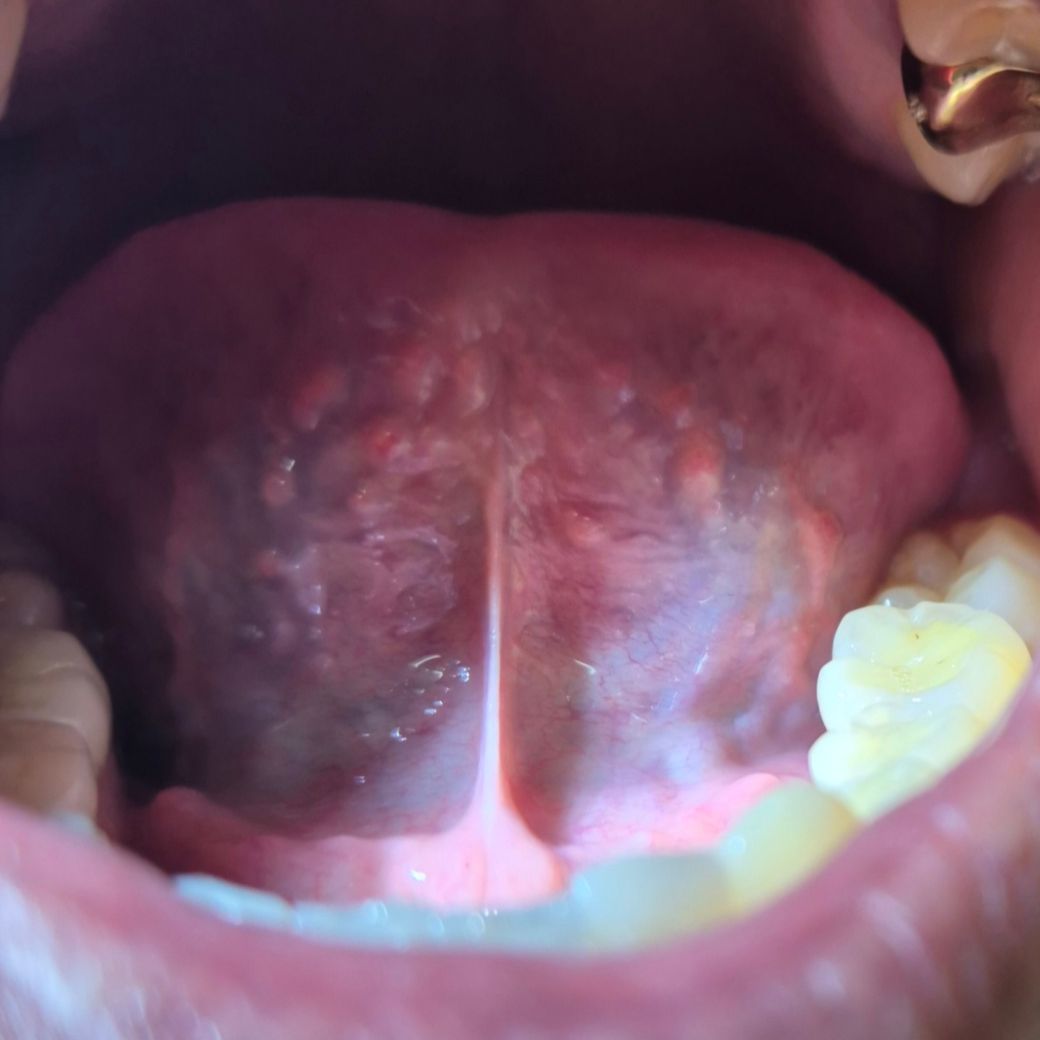

의사 선생님들 혀바닥 밑에 돌기(여드름) 있는데 괜찬은 건가요??

의사 선생님들 혀바닥 밑에 돌기(여드름) 있는데 괜찬은 건가요?? 작년 부터 알았는데 다 있는 줄 알았어요..

크게 신경 안썻는데 혹시 괜찬은건가요?? 통증 x 가그린 자주 하는데 쓰라리거나 아프거나는 없습니다ㅠ

사진으로는 정확한 진단 불가한점 양해바랍니다. 혀 밑에 생기는 돌기는 보통 무해하지만, 혀 한쪽 면에만 생긴 경우에는 암성인지 확인을 위해 검사를 받아야 합니다. 양쪽 다 있으시니 크게 걱정할 필요는 없어보이나 정확한 진단을 위해선 이비인후과 검사를 받아보시는게 좋습니다. 감사합니다